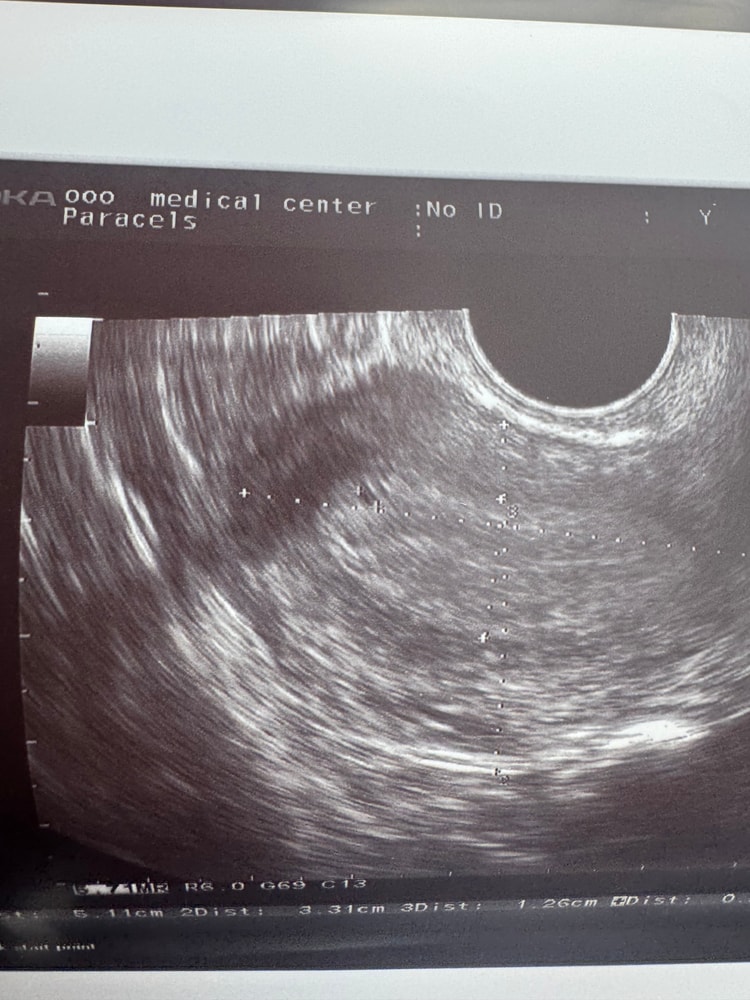

Узи

тесты отрицательные, либо призрачные полоски, сходила на узи, что б исключить патологию

Врач увидела точку, сказала возможно оно, а может и нет, размер 0,21 см, эндометрий 9,3 мм